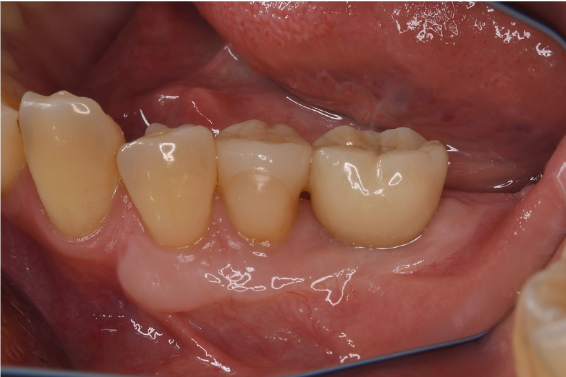

症例3

| 項目 | 詳細 |

|---|---|

| 患者様データ | 50代 男性 |

| 来院時の主訴 | 「左下で噛むと違和感がある。」 |

| 医院の診断 | 左下第二大臼歯の歯根破折 |

| 通院期間 | 9か月 |

| 来院回数 | 12回 |

| 治療費 | 総額:835,000円(税抜) 【内訳】 インプラント埋入手術250,000円、GBR(骨再生手術)150,000円、2次手術+FGG(遊離歯肉移植術)55,000+60,000円、仮歯30,000円、インプラント上部構造(セラミッククラウン)170,000円、隣在歯セラミッククラウンのやりかえ120,000円 |

| リスクと副作用 | 定期的なメンテナンスが必要、術後若干の腫れと痛み |

| ここがこだわりのポイント!☝ | インプラント周囲に角化歯肉と言われる健常な歯肉がなかったので、口蓋からの歯肉移植を行っています💡この角化歯肉がないと、インプラントをしてもうまく歯磨きができないことがあります。 |